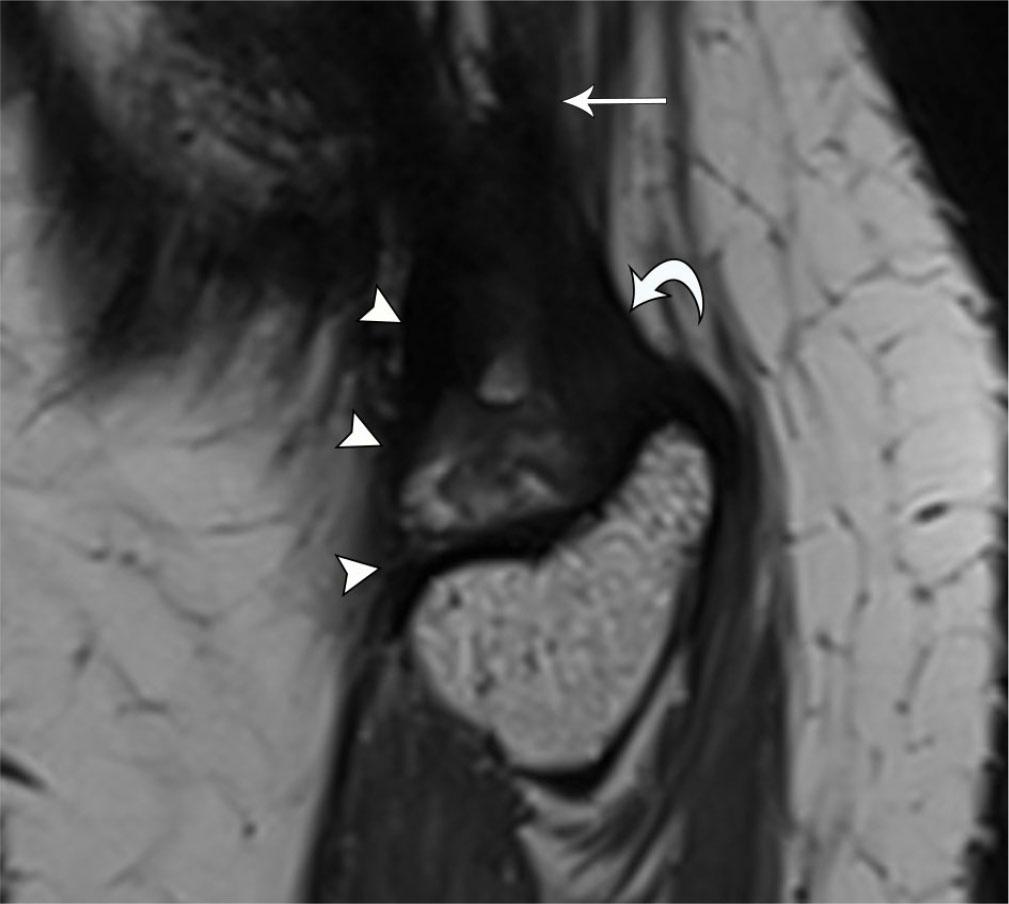

A sudden displacement of anatomic structures during knee joint motion results in a snapping sensation. Recurrent snapping potentially leads to pain, discomfort, and limitation of activities. Sources of snapping include extra-articular structures, like the popliteus tendon, pes anserinus, and iliotibial band(3). Intra-articular etiologies include menisci, plicae, tumors, and joint bodies(44). One of the most common sources of extra-articular knee snapping is the distal long head biceps femoris tendon(45). The snap occurs during knee extension, and clinical examination shows abrupt translocation of the biceps tendon over the fibular head(46). Dynamic real-time visualization of the tendon with US confirms the snapping source during range-of-motion movements. Once the source of snapping is identified, MRI can serve as a useful adjunct for the assessment of anatomy prior to surgical intervention, in particular the evaluation of the direct (fibular) and anterior (tibial) arms of the distal biceps femoris tendon (Fig. 13, Video 1(47). Other associations include congenital absence of the direct arm, fibular head hypertrophy, and too-distal bifurcation of the two arms(45).

Fig. 13.

33-year-old female with snapping sensation at the lateral knee. Dynamic US imaging (see Video 1) shows snapping of the tibial arm of the biceps femoris tendon. Note initial orientation of the probe in the longitudinal plane before turning to short axis before imaging about the fibular head. Sagittal PD SPACE MR image shows thickened tibial arm (arrowheads) bifurcating from the biceps femoris tendon (arrow) and coursing anterior to the fibular arm (curved arrow)